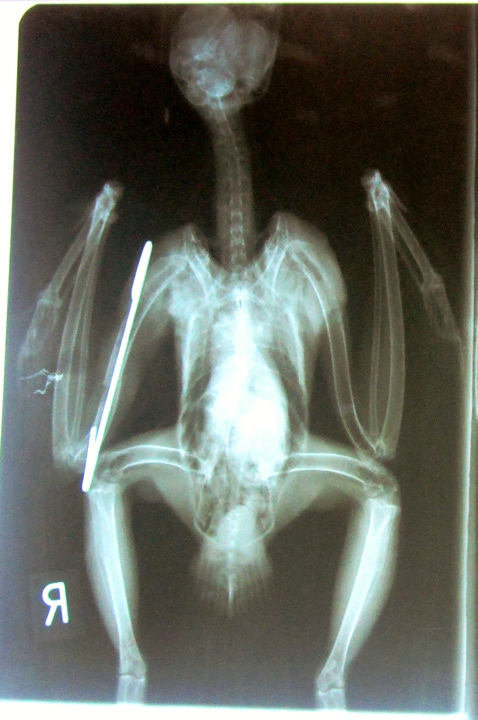

Αυτή τη βδομάδα στάλθηκε από την Άνδρο στην ΑΝΙΜΑ μια

Γερακίνα με ανοιχτό κάταγμα από ατύχημα.

Ο κτηνίατρος της ΑΝΙΜΑ έκανε

ήλωση στη φτερούγα και ελπίζουμε για το καλύτερο!

η ακτινογραφία όπου φαίνεται η ήλωση .